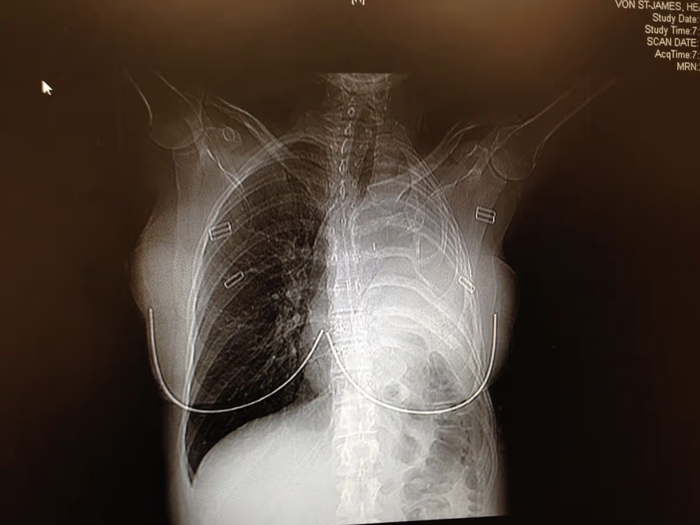

การไปพบแพทย์นำมาซึ่งการตรวจร่างกายและเอกซเรย์คอมพิวเตอร์ (CT scan) แพทย์พบเนื้องอกขนาดใหญ่ใกล้กับปอดของเธอ และวินิจฉัยว่าเธอเป็น “โรคมะเร็งเยื่อหุ้มปอด” (Pleural Mesothelioma) ซึ่งเป็นมะเร็งชนิดลุกลามดุร้ายที่มีสาเหตุมาจากการสัมผัสแร่ใยหินโดยตรง

วันที่เข้ารับการผ่าตัดในเดือนกุมภาพันธ์ ปี 2006 เป็นวันที่ยากลำบากและโดดเดี่ยวที่สุดในชีวิตของเธอ แพทย์ต้องผ่าตัดเอาปอดซ้ายของเธอออกไปทั้งข้าง พร้อมกับซี่โครง 1 ซี่, เยื่อหุ้มปอดส่วนที่มีเนื้องอก, เยื่อหุ้มหัวใจ และชิ้นส่วนของกะบังลมออก (โดยใช้ Gore-Tex ทางการแพทย์ทดแทน) หลังจากการผ่าตัด เธอต้องผ่านกระบวนการทำเคมีบำบัดแบบล้างช่องอกด้วยความร้อน (Heated chemotherapy) ที่แพทย์เรียกว่า “Shake and Bake” ตามด้วยการทำเคมีบำบัดอีก 4 รอบ และการฉายรังสีอีก 30 ครั้ง

ปัจจุบัน เฮเธอร์รอดชีวิตจากการเป็น มะเร็งเยื่อหุ้มปอด มาได้กว่า 20 ปีแล้ว ซึ่งแพทย์บอกว่าเป็นเคสที่หาได้ยากมากสำหรับผู้ป่วยมะเร็งชนิดนี้ แม้การมีปอดเพียงข้างเดียวจะทำให้เธอมีข้อจำกัดในชีวิต เช่น ไม่สามารถวิ่งได้ เหนื่อยหอบง่ายเมื่อขึ้นบันได หรือไม่สามารถยกของหนักได้ แต่เธอก็ใช้ชีวิตที่เหลืออยู่นี้เป็นวิทยากรรณรงค์ให้ผู้คนตระหนักถึงภัยร้ายของแร่ใยหิน (น่าเศร้าที่พ่อของเฮเธอร์ ได้เสียชีวิตลงในปี 2014 จากโรคมะเร็งไต ซึ่งแพทย์เชื่อว่าอาจมีส่วนเกี่ยวข้องกับการสัมผัสแร่ใยหินเช่นกัน)